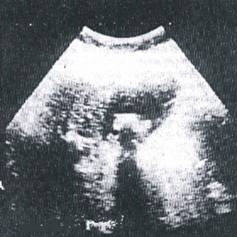

- echografia este astazi explorarea cea mai uzuala in patologia biliara datorita

urmatoa relor considerente:

este metoda neinvaziva

este bine tolerata (nu exista inconvenientul iradierii sau al iodismelor, poate fi efectuata si in plin puseu al colecistitei acute repetandu-se de cate ori este nevoie)

este practicabila si la bolnavii cu bilirubinemia peste 3 mg%

permite stabilirea algoritmului mijloacelor diagnostice la bolnavii icterici (cai biliare nedilatate icter posibil medical; cai biliare intrahepatice dilatate se indica colangiografie transparietohepatica; CBP dilatata se indica ERCP)

exploreaza concomitent si alte organe abdominale

depisteaza si alte leziuni ce ar putea fi implicate in suferinta biliara (chist hidatic hepatic, ciroza hepatica, pancreatita cronica sau chiar acuta, litiaza pancreatica, cancer de cap pancreatic, etc.)

limitele echografiei constau in lipsa de precizie a explorarii CBP (mai ales a coledocului retroduodenal);